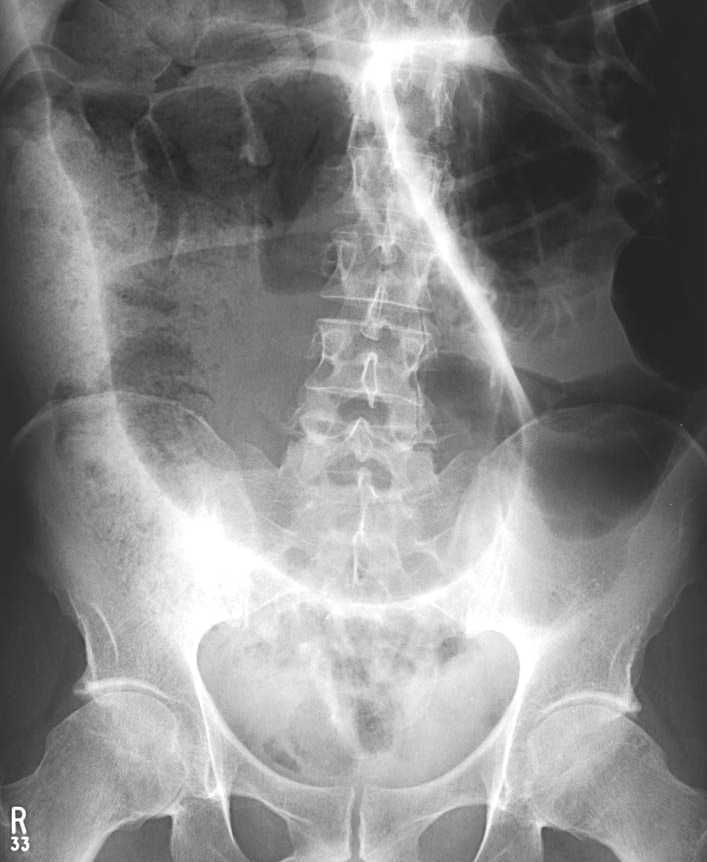

On examination he has abdominal swelling, guarding and numerous audible bowel sounds.

What is the diagnosis?

Sigmoid volvulus